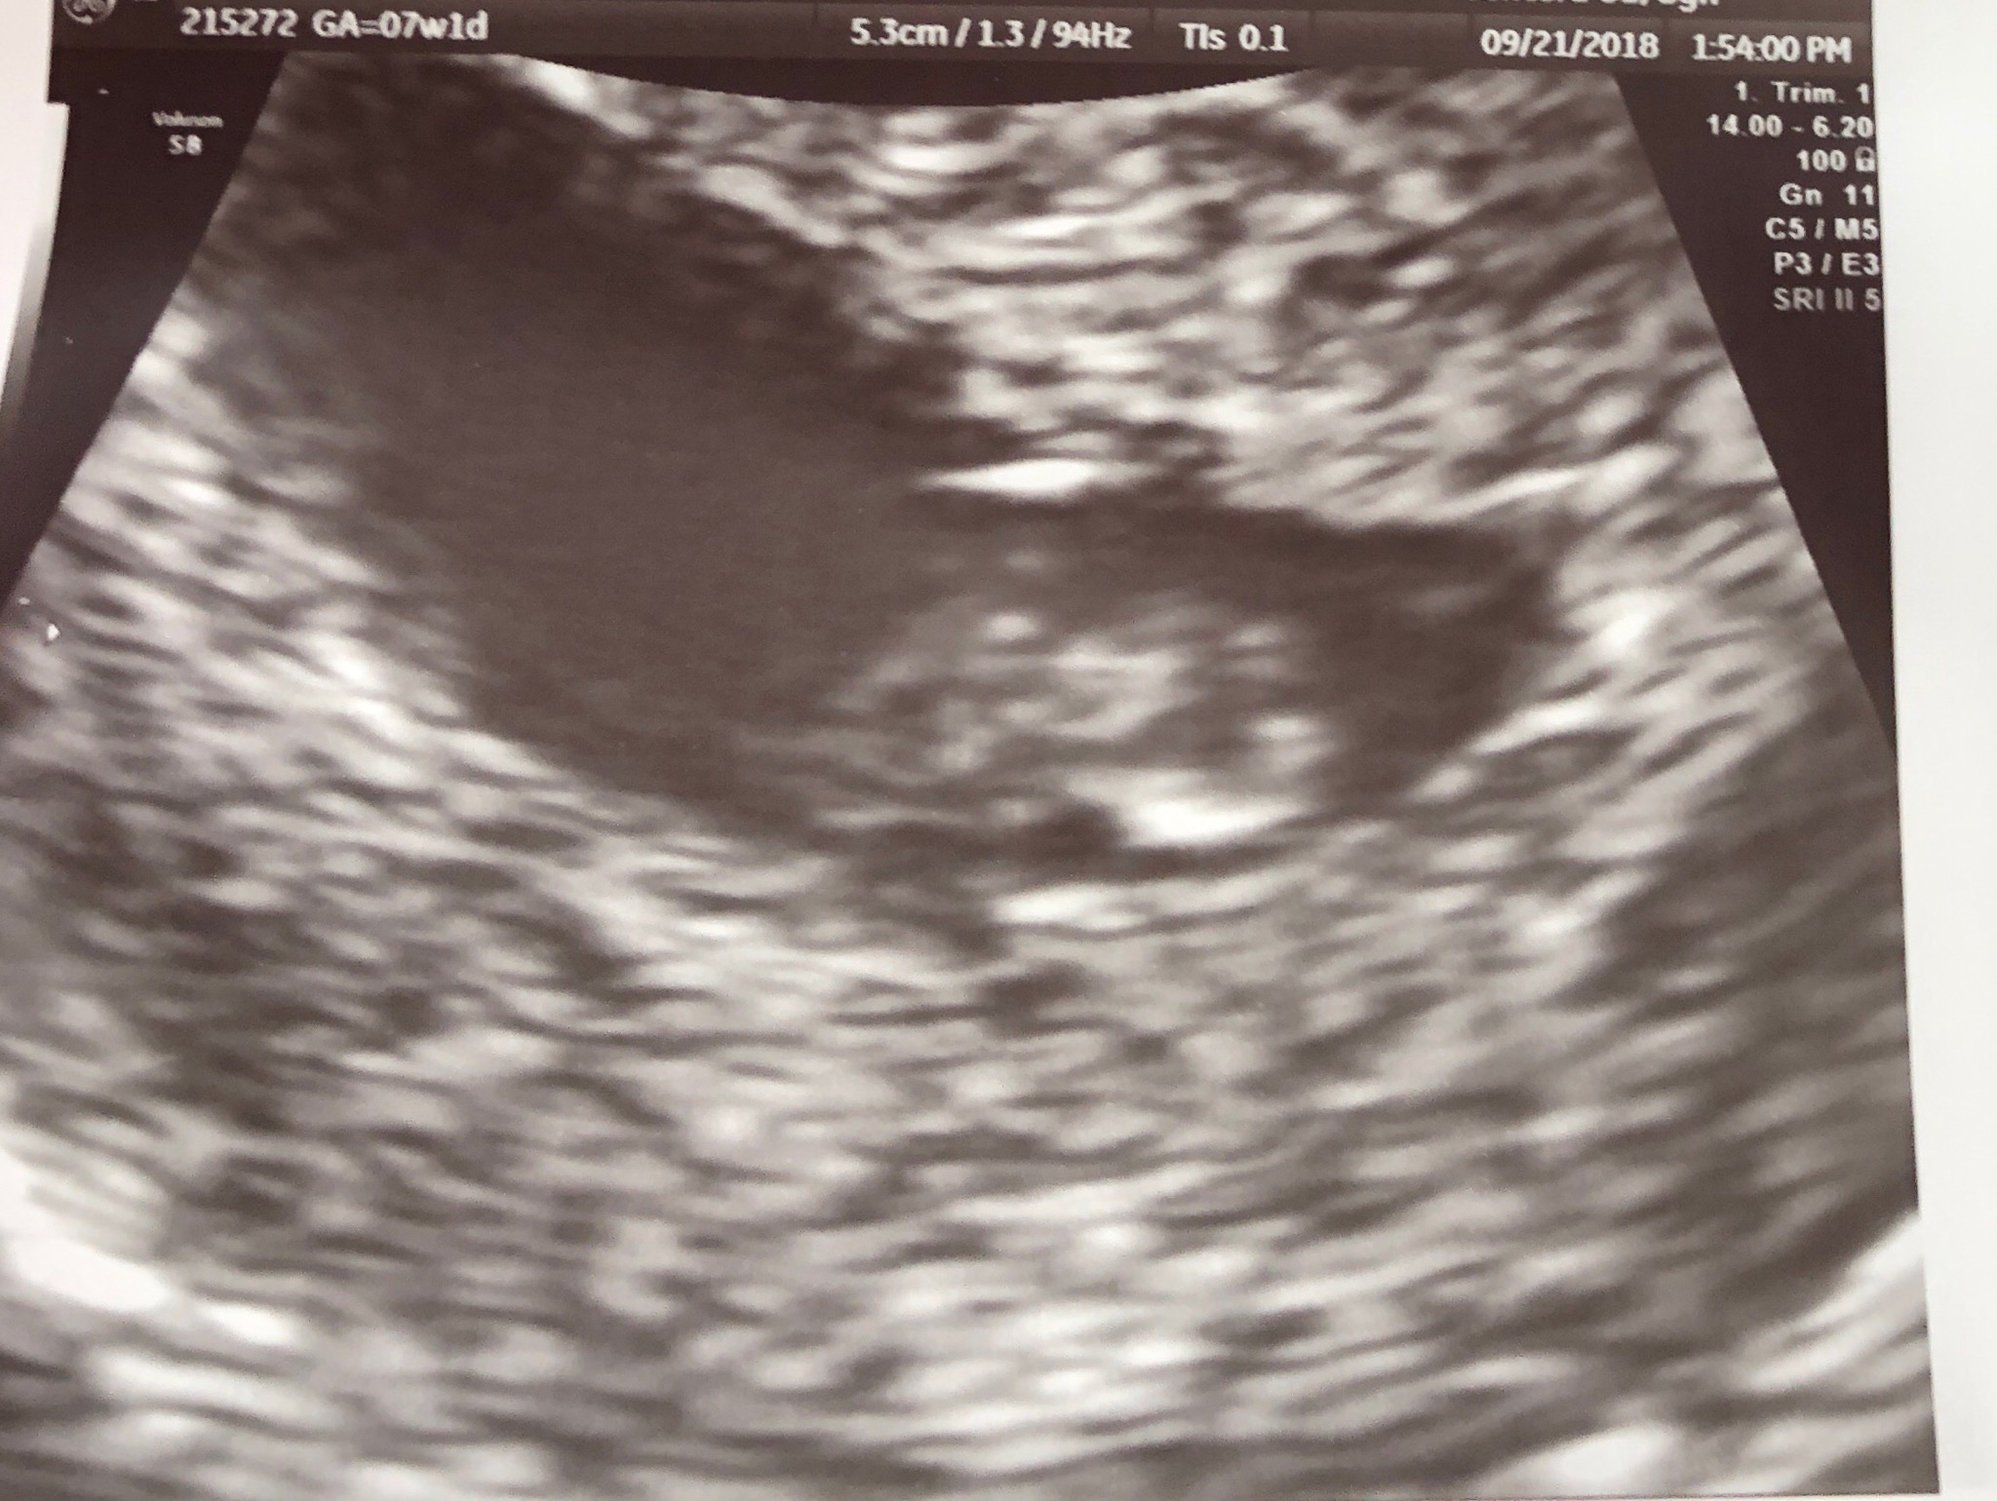

We had our first ultrasound today! We were estimating 6w1d today, and we measured that exactly! The pictures we got don’t show the baby very well because the US tech had measuring marks on them. She measured the heartbeat at 105. Such a relieving feeling seeing that little flicker!